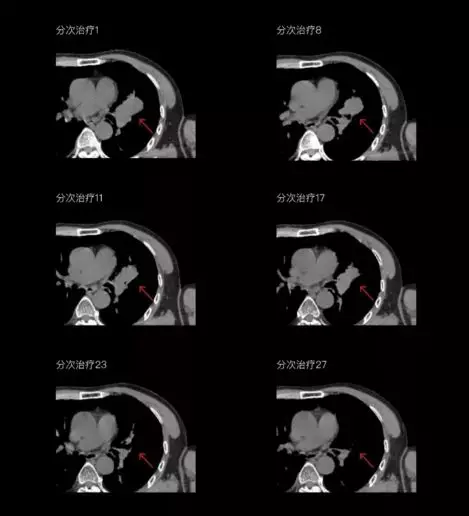

個體化自適應(yīng)放療

一體化CT-linac讓自適應(yīng)放療ART概念變?yōu)楝F(xiàn)實?;颊呷煶虪顟B(tài)監(jiān)控,適時在線調(diào)整治療計劃,精準(zhǔn)控制治療劑量,為患者動態(tài)定制個體化治療方案。uAI賦能智能勾畫和自動計劃,秒級勾勒靶區(qū)和危及器官,大幅縮短自適應(yīng)放療時間。

聯(lián)影CT-linac全程監(jiān)測治療過程病灶的變化,及時調(diào)整和優(yōu)化治療方案